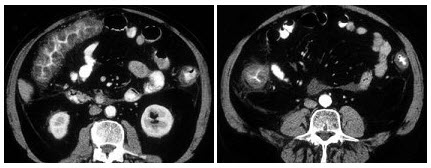

17、单项选择题

男,67岁,排便习惯改变,血便3月入院,CT检查如图所示,下列说法错误的是()

A.直肠肠腔局限性增厚

B.其表面欠光整,边界欠清晰

C.可做直肠指检及活检以确定病变性质

D.此为直肠息肉

E.此为直肠癌

19、单项选择题

如图所示,这两个时相提示()

A.肾细胞癌